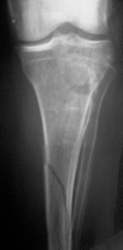

Tibiakopffraktur mit Tibiaschaftfraktur. Geschlossene Nagelung. Nach 3 Wochen volle Belastung. Die rechten zwei Röntgenbilder zeigen den Befund nach einem Jahr.